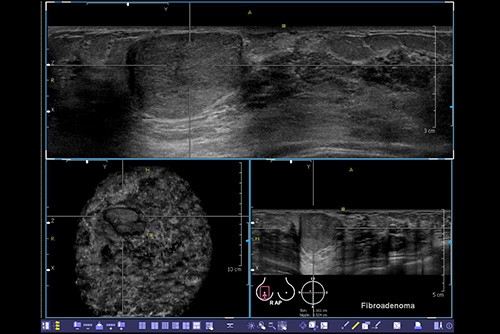

A breast ultrasound uses high-frequency sound waves to look inside your breast to detect cancers, cysts, or masses. An ultrasound technician uses a sound-emitting probe to conduct the test. The sound waves travel through the breast, and then they are converted into images on a screen. The ultrasound exam can demonstrate whether a lump is a solid or a liquid filled mass such as a cyst, leading to different treatments. Consistent with studies that show having a breast ultrasound with an annual mammogram can find more small cancers than a mammogram alone, a high percentage of the cancers PINK finds are found with ultrasound.

Elastography is a non-invasive technology projecting ultrasound waves into your breast to characterize cysts vs. other masses in the tissue. Cysts are composed of fluid and do not require the same treatment as other masses. If the mass is solid, and potentially cancer, it will appear stiff compared to surrounding tissue.